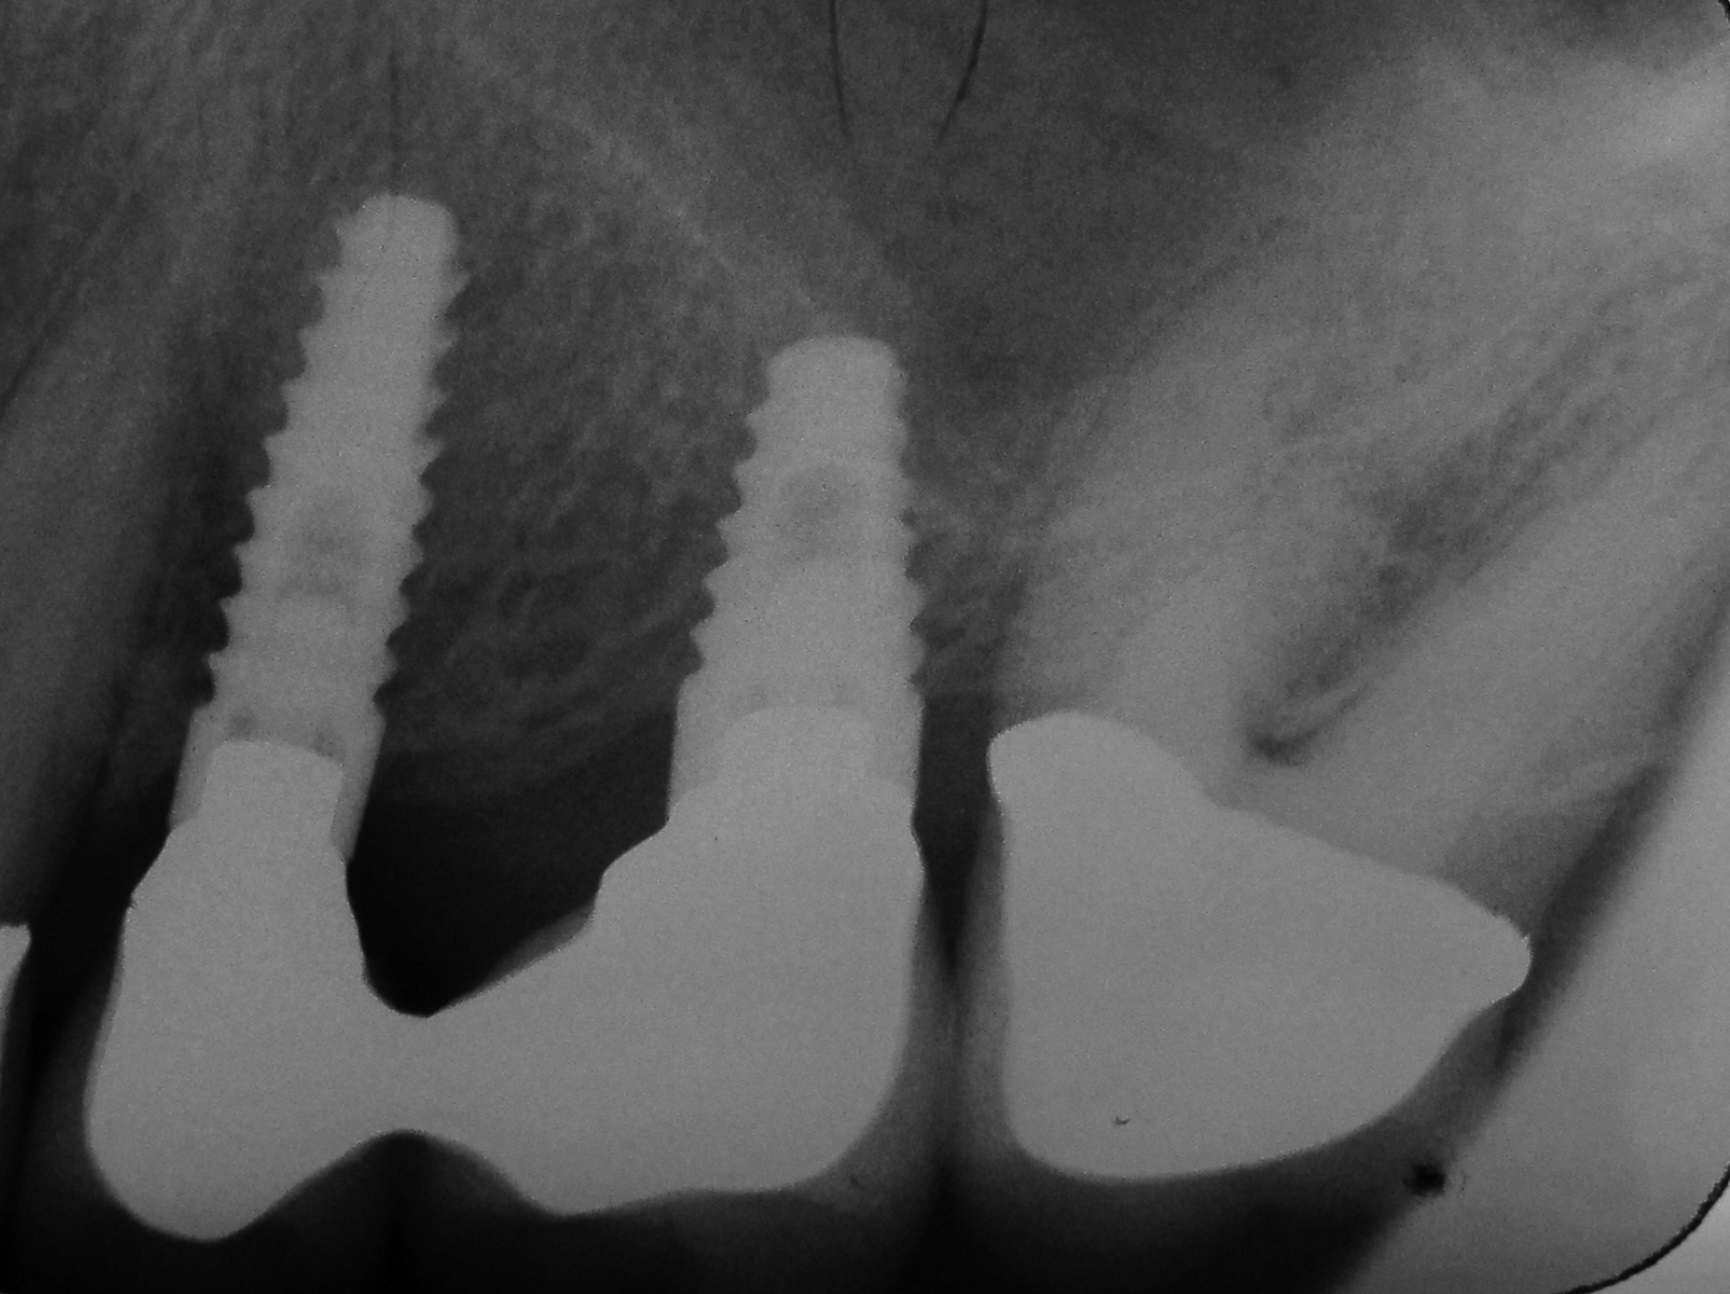

01/06 - Pre-operative radiograph.Treatment of a periodontal bone defect adjacent to an edentulous site using Straumann® Emdogain® - Prof. Dr. P. Windisch

Radiographic view before periodontal regenerative therapy with Straumann® Emdogain®. A deep intrabony defect appeared mesially and distally on the left mandibular first premolar. Pre-surgical probing measured 8 mm. The defect morphology presented as well-contained.

Pre-operative radiograph. Intrabony defect on the mesial aspect of tooth 14.